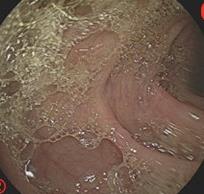

摘要:目的 探讨利那洛肽联合西甲硅油与复方聚乙二醇电解质散(PEG)对便秘患者肠道清洁效果的有效性和安全性。方法 采用前瞻性随机对照试验,通过单盲法,纳入2023年4月-2024年8月于该院消化内镜中心行结肠镜检查的便秘患者383例,随机分为常规组(128例)、实验A组(128例)和实验B组(127例)。常规组采用3 L PEG(Ⅰ)溶液,实验A组采用290 μg利那洛肽 + 2 L PEG溶液,实验B组采用290 μg利那洛肽 + 30 mL西甲硅油+2 L PEG溶液。比较3组患者的肠道准备效果[Boston肠道准备量表(BBPS)评分和去泡效果]、病变检出率、首次排便间隔时间、排便次数、盲肠插管成功率、进镜时间、退镜时间、不良反应发生率和重复检查意愿等。结果 3组患者BBPS评分比较,差异无统计学意义(P > 0.05);实验B组的去泡效果评分明显低于常规组和实验A组,差异均有统计学意义(P < 0.05);实验B组的病变总检出率和息肉检出率明显高于常规组和实验A组,差异均有统计学意义(P < 0.05);常规组的首次排便间隔时间明显长于实验A组和实验B组,差异均有统计学意义(P < 0.05);3组患者排便次数比较,差异无统计学意义(P > 0.05);3组患者盲肠插管成功率均为100.0%,进镜时间相当,差异均无统计学意义(P > 0.05);实验B组的退镜时间明显短于常规组和实验A组,差异均有统计学意义(P < 0.05);常规组腹胀腹痛发生率和不良反应总发生率明显高于实验A组和实验B组,差异均有统计学意义(P < 0.05);常规组重复检查意愿率明显低于实验A组和实验B组,差异均有统计学意义(P < 0.05)。结论 290 μg利那洛肽联合30 mL西甲硅油与2 L PEG溶液方案在便秘患者肠道准备上具有优势,较3 L PEG溶液和290 μg利那洛肽+2 L PEG溶液方案,可获得更好的肠道清洁效果,且安全性和患者重复检查意愿率高,可作为便秘患者肠道准备的推荐方案。